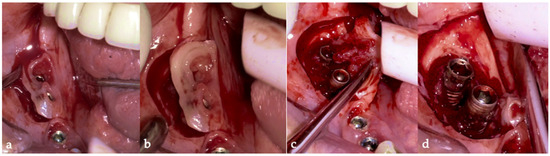

The surgical step began with local anesthesia (Lidocaine 2% with 1:100,000 epinephrine—Henry Schein Inc., New York, NY, USA) locally administered; the screw-retained crowns on the implants were removed to facilitate proper surgical access (Figure 9). The surgical site was assessed in order to provide a minimally invasive buccal flap design, which was favorable in this case, as it effectively executed the Quadrant protocol.

The choice of flap design was crucial for optimal healing and patient outcomes. A buccal single flap (BSF) approach offers distinct advantages over the traditional midcrestal flap technique; BSF involves a precise incision on the buccal side, primarily targeting healthy tissue. This method enhances the visibility of the surgical area and minimizes trauma to inflamed tissues, facilitating easier suturing and manipulation. BSF permits better healing and reduces postoperative complications by avoiding incisions through fragile and inflamed tissues. Additionally, preserving the periosteal blood supply in this approach may minimize the loss of crestal ridge width and height, contributing to improved surgical outcomes. BSF design also reduces the injury to the keratinized tissue [50]. The advantages of the BSF are the reduced tissue trauma by limiting incisions to healthy tissue, minimizing damage to inflamed areas, leading to better healing and patient comfort; enhanced surgical visibility, providing a clear view of the surgical site, allowing for precise manipulation and suturing; the preservation of blood supply, maintaining the integrity of the periosteal blood supply, which supports bone preservation and reduces the risk of crestal bone loss [51] (Figure 10a,b).

Then, the BSF was reflected to the lingual side (Figure 10c,d), exposing the surgical and infected site. Significant calculus deposits and plaque were noted on and around the implant surfaces. Then, with the screwed pin (hinge) in position, the implantoplasty was performed through the Quadrant protocol using the novel iMPACT device to renew the implant surface, transform it into a machined surface, and contour the surrounding bone (Figure 11).

Figure 10. (a) BSF incision; (b) BSF raised; (c) BSF moved from buccal to lingual; (d) BSF raised exposing the implants and local bone.